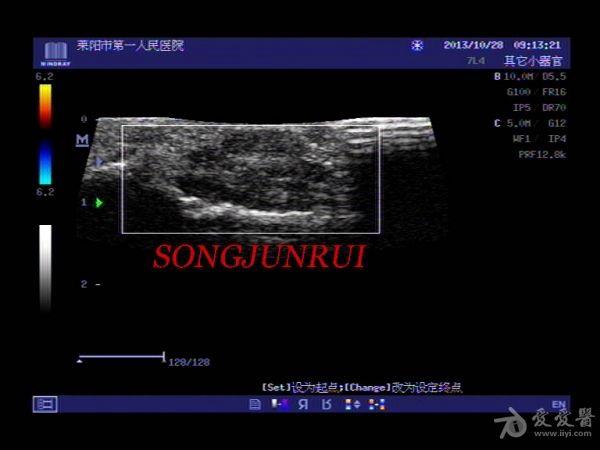

超声入门贴202-----手指腱鞘巨细胞瘤(手术病理)

女,43岁,右手食指中节近节指关节处明显肿胀一年,近一个月增大明显来诊

触诊:有结节感,加压疼痛明显

手术剖开见肌腱附着结节样淡黄色实性组织,范围较广泛,边界不清,病理电话随访腱鞘巨细胞瘤。